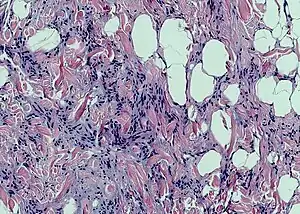

梭形细胞脂肪瘤

梭形细胞脂肪瘤(spindle cell lipoma)是一种无症状、生长缓慢的皮下肿瘤,多見於老年男性的背部、颈部和肩部。[1]:625[2]